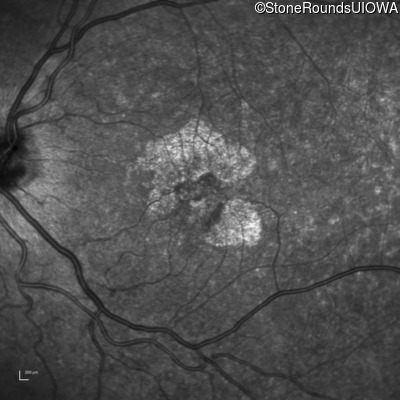

Infrared Fundus Photograph - Left - 20/20 -1

Exemplar